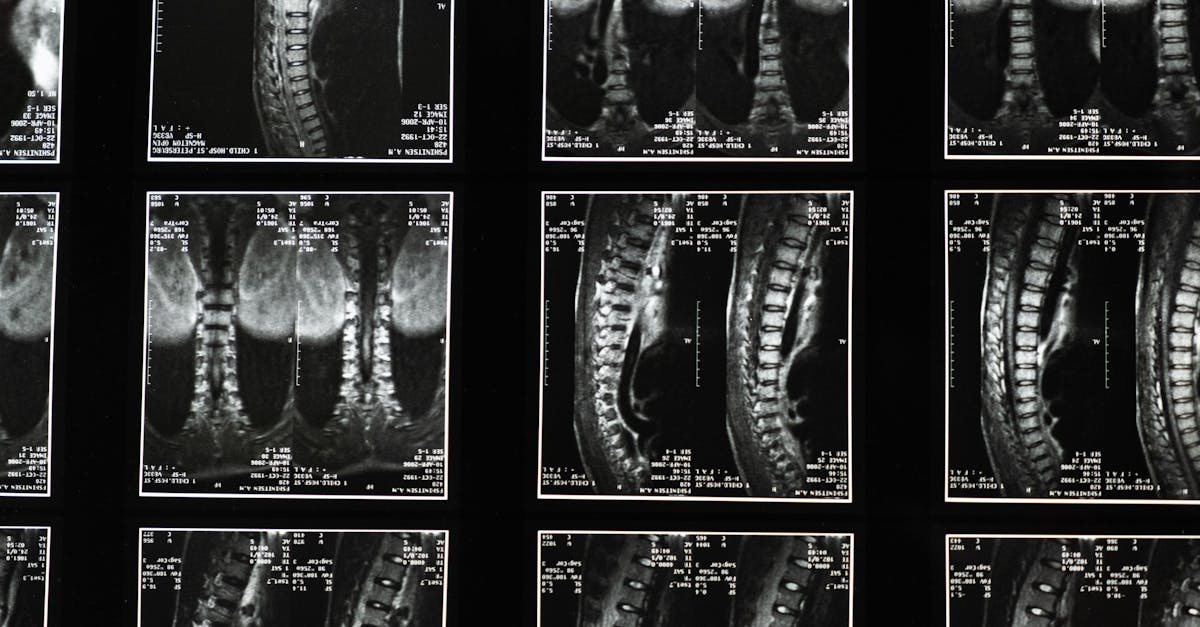

lombalgies , desciatique et de l’inconfort lié auxhernies discales. Des études montrent qu’environ 80 % des adultes souffrent de lombalgies invalidantesà un moment ou à un autre de leur vie. Cette méthode holistique met l’accent sur des exercices de renforcement musculaire et des techniques de correction posturale, telles que les bascules pelviennes et les techniques de levage appropriées, afin de soulager la douleur et d’améliorer le bien-être général. En intégrant des étirements efficaces pour les douleurs lombaires et des solutions ergonomiques, Pulse Align aide les personnes à retrouver leur santé et à optimiser leur confort au quotidien. Découvrez comment cette approche globale du soulagement de la sciatique peut améliorer votre qualité de vie et atténuer des affections telles que la sténose du canal rachidien et le syndrome du piriforme. Découvrez des stratégies efficaces pour gérer la sciatique, notamment des exercices, des traitements et des conseils d’hygiène de vie pour améliorer votre qualité de vie. Découvrez les causes, les symptômes et les remèdes naturels pour soulager l’inconfort. « `html Découvrez des méthodes naturelles pour améliorer votre posture avec Pulse Align Vous cherchez à améliorer votre bien-être grâce à une meilleure posture et à des stratégies efficaces pour un équilibre naturel ? Pulse Align propose une approche unique de recalibrage neuromusculaire, vous permettant de retrouver l’harmonie que votre corps mérite grâce à une stimulation douce. Cette technique favorise un fonctionnement optimal et accompagne un parcours holistique vers le bien-être. Comprendre l’approche Pulse Align Chez Pulse Align, nous nous concentrons sur les principes de tonicité symétrie et équilibre naturel . Grâce à une technologie de pointe et à une stimulation douce, notre approche aide nos clients à rétablir l’équilibre de leur corps. Cela aligne efficacement le système musculaire, ce qui peut favoriser une amélioration globale du confort et de la mobilité.Bienfaits holistiques de Pulse Align Au cœur de nos services se trouve notre engagement envers les capacités naturelles de guérison de votre corps. Notre méthodologie renforce l’interdépendance du bien-être de chaque client, offrant un espace bienfaisant où les tensions peuvent se dissiper. De nombreux clients déclarent se sentir plus à l’aise et plus stables à mesure que leur posture s’améliore naturellement au fil du temps. En adoptant la méthode Pulse Align, les clients adoptent un mode de vie plus énergisé et moins inconfortable. Témoignages clients Nos clients partagent fréquemment leurs expériences positives avec Pulse Align, soulignant que grâce à notre approche holistique, ils ont amélioré leur posture naturellement et ont bénéficié d’une plus grande souplesse. Par exemple, un client a mentionné comment il a pu réduire ses douleurs cervicales et s’est senti plus à l’aise pour s’adonner à des activités qui lui semblaient auparavant difficiles. Ces témoignages illustrent le soutien apporté par le programme Pulse Align sur le chemin vers un meilleur bien-être général. Rejoignez la communauté Pulse Align Prêt à découvrir les bienfaits de Pulse Align pour vous-même ou votre famille ? Nous vous invitons àtrouver une clinique Pulse Align près de chez vous.

- Comprendre le lien entre sciatique et lombalgie. La sciatique est souvent due à des affections telles qu’une hernie discale, une sténose spinale ou un syndrome du piriforme. Ces problèmes peuvent entraîner une inflammation et une compression nerveuse, entraînant des douleurs lombaires invalidantes.

Les protocoles de traitement spécifiques de la sciatique dépendent largement des causes sous-jacentes des lésions nerveuses. Si certains professionnels de santé peuvent recourir à des médicaments tels que des anti-inflammatoires ou des relaxants musculaires pour traiter les cas graves, des données probantes soulignent les bienfaits de la kinésithérapie, des ajustements chiropratiques et des étirements pour une réduction significative de la douleur. Ajustements vertébraux chiropratiques :Différents types de ruptures ou de hernies discales peuvent entraîner des douleurs nerveuses plus ou moins intenses. Certaines blessures peuvent nécessiter une évaluation professionnelle pour un diagnostic correct. Suite à l’évaluation, un chiropracteur peut réaligner les disques intervertébraux afin de prévenir l’irritation nerveuse et de cibler efficacement la cause de la douleur.

et trouvez un centre près de chez vous ici : Recherche de centre . Transformez votre rétablissement grâce à la technologie de décompression vertébrale de TAGMED TAGMED propose une thérapie de décompression vertébrale avancée, une solution non chirurgicale spécialement conçue pour traiter les problèmes discaux modérés à sévères, notamment les hernies discales et les bombements discaux. En réduisant doucement la pression exercée sur les disques et les nerfs affectés, cette technique spécialisée améliore la mobilité, soulage la douleur et favorise le processus naturel de guérison. Si vous avez atteint un palier avec d’autres thérapies, découvrez comment l’approche de décompression fondée sur des données probantes de TAGMED peut vous aider à reprendre une vie active et confortable. Avez-vous essayé des traitements conventionnels et souffrez-vous toujours de douleurs dorsales persistantes dues à une discopathie sévère ?Mécanisme d’action La décompression neurovertébrale de TAGMEDapplique une force de traction contrôlée et progressive sur la colonne vertébrale, augmentant ainsi efficacement l’espace entre les vertèbres. Cette méthode réduit la pression sur les disques intervertébraux

et les racines nerveuses tout en favorisant une meilleure circulation des fluides dans la zone ciblée. Cette circulation accrue contribue à réduire l’inflammation et à soulager la douleur, offrant une solution fiable et non invasive aux personnes souffrant de douleurs dorsales chroniques. Avantages spécifiques Cette approche non invasive soulage efficacement la douleur chronique et les symptômes liés à des affections telles que la sténose spinale